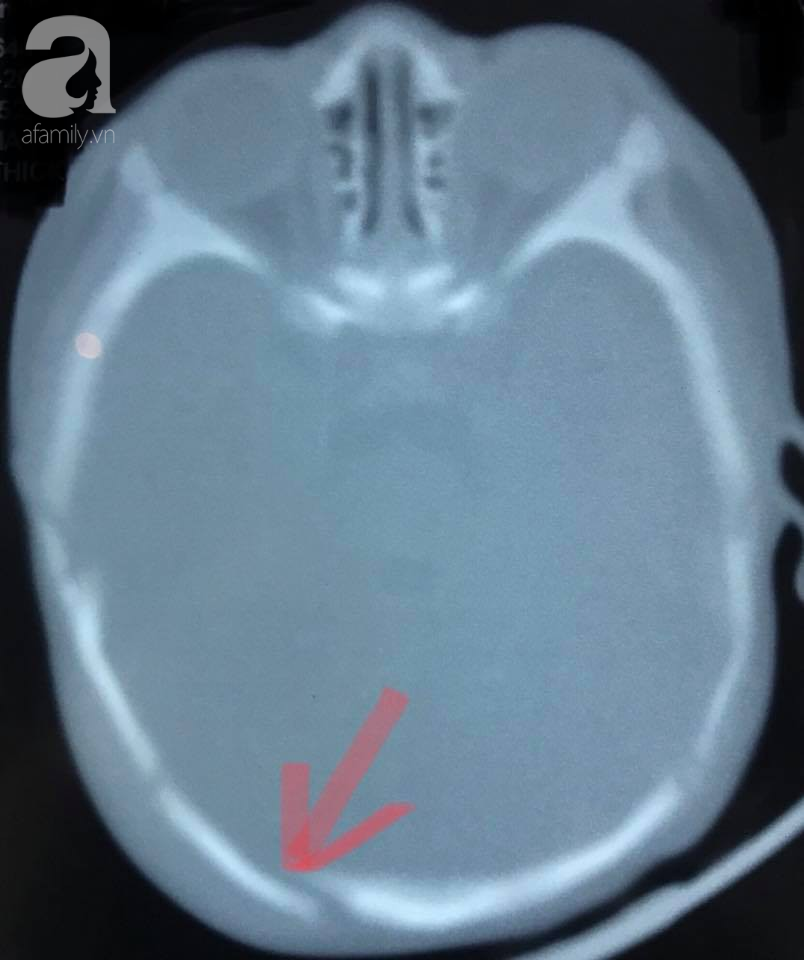

05/08/2018 03:05TP.HCM: Cha không giữ được bình tĩnh, 'lỡ tay'làm con trai 2 tháng tuổi xuất huyết não vì quấy khóc không chịu ngủ

Bác sĩ Lê Quang Mỹ, khoa Ngoại thần kinh, Bệnh viện (BV) Nhi đồng 2 (TP.HCM) cho biết sự việc đau lòng này xảy ra với một bệnh nhi 2 tháng tuổi, ngụ TP.HCM.

Tối hôm xảy ra sự việc, bé trai con họ cứ liên tục quấy khóc không chịu ngủ. Dỗ mãi không được, phần vì đi làm cả ngày mệt mỏi nên trong lúc không kiểm soát, người cha đã "chạm nhẹ" vào đầu con.

Đứa bé mới 2 tháng tuổi nên chỉ cần một lực nhỏ của người lớn đã bị chấn thương. Sau hành động bộc phát, người cha hốt hoảng ẵm con đưa đi cấp cứu. Theo lời người cha, lúc đó anh không hoàn toàn không uống rượu bia.

Thời điểm nhập viện, bệnh nhi thiếu máu nhiều, lơ mơ, phải thở máy hỗ trợ vì xuất huyết não. Sau khi được truyền máu cũng như hồi sức tích cực hơn 1 tuần, bé trai có thể tự thở, được chuyển sang điều trị tại khoa Ngoại thần kinh 1 tuần.

"Bé đã được cho xuất viện khi tự bú, tự thở được. Dù vậy vẫn cần tái khám để theo dõi các vấn đề về động kinh, di chứng vận động…" – Bác sĩ Mỹ nói.